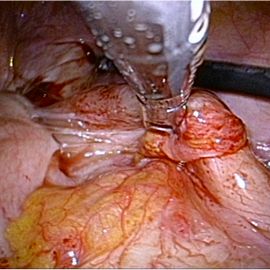

[慢性虫垂炎(急性増悪)] 手術:単孔式腹腔鏡下回盲部切除術

および虫垂腫瘍疑いと診断した。症状の憎悪も認め、単孔式腹腔鏡下回盲部切除術を施行した。

手術画像